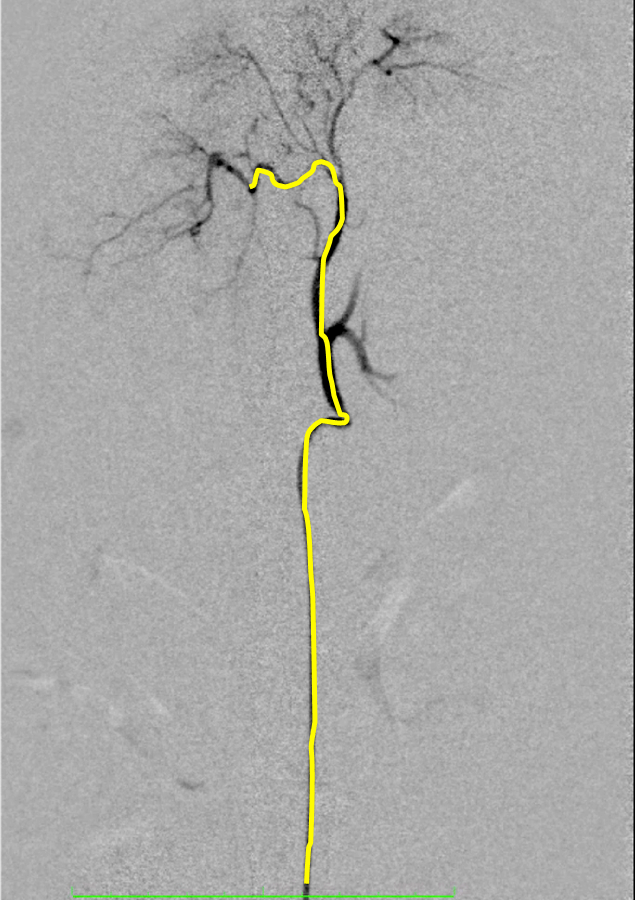

【実施症例】腰下リンパ節に転移した血管肉腫に対する動注療法

ゴールデン・レトリーバー、11歳、雄。

腰下リンパ節に転移した血管肉腫。

腫瘍の頭側の腹大動脈にリザーバーを設置し、抗がん剤の投与を行った。腫瘍は1/3以下に縮小が認められた。

血管肉腫が転移した腰下リンパ節

腫瘍陰影(DSA画像)

実施前

実施後